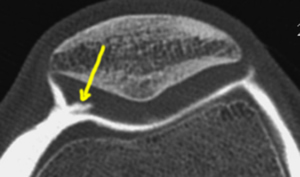

Images de chondropathies en IRM

Les chondropathies sont découvertes par le radiologue sur une IRM.

L'arthroscanner est un examen plus précis, qui n'a pas d'intéret, sauf dans les très rares cas, où se discute un indication opératoire. Par exemple, pour vérifier l'état cartilagineux de l'autre compartiment, avant une osteotomie de valgisation.